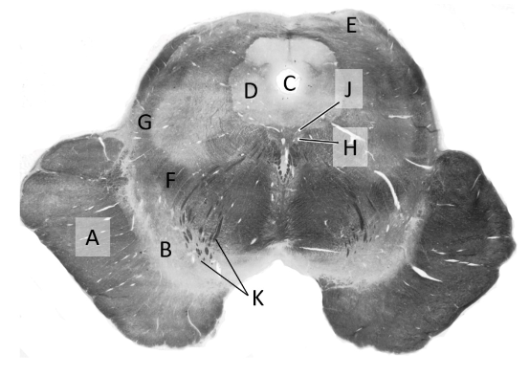

at what level is this?

spino-medullary junction

what is a?

spinal trigeminal nucleus

what is b?

nucleus cuneatus (sm)

what is c?

fasciculus gracilis (sm)

what is e?

pyramidal decussation

what is f?

spinocerebellar & (more medial) spinothalamic tract